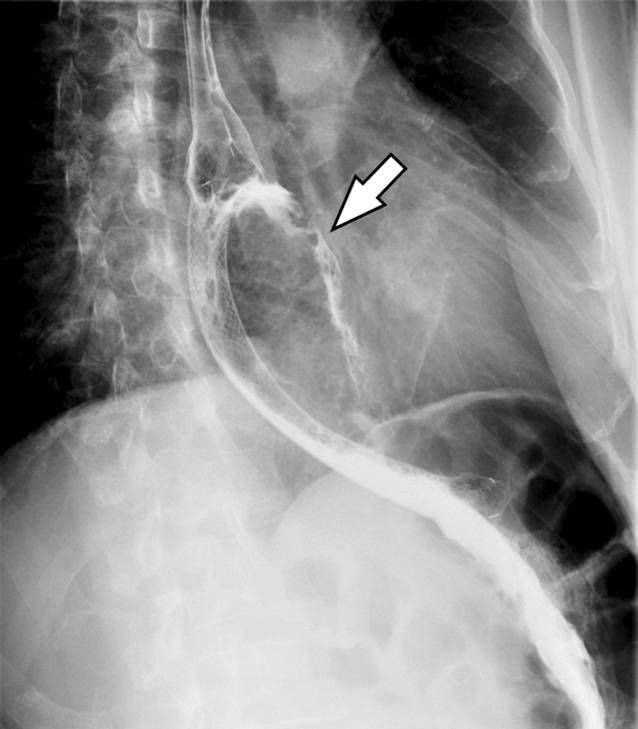

Abb. 5

Endoskopische Stentimplantation zur Schluckpalliation: Man erkennt einen guten Kontrastmitteltransit durch den Stent in den Magen. Es verteilt sich auch Kontrastmittel in der nekrotischen Raumforderung (Pfeil)